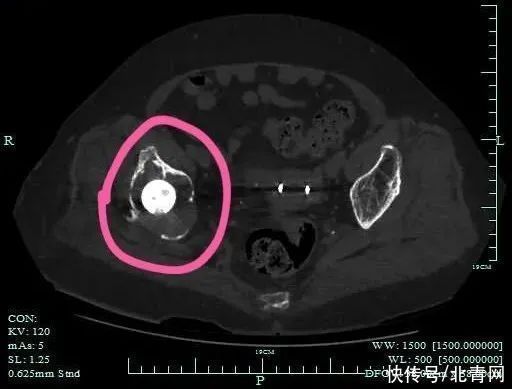

CT显示,多处骨骼缺损

原来,12年前,陈奶奶因摔倒导致右侧髋部骨折,在当地医院接受了人工髋关节置换术,手术后,陈奶奶行走生活并无异常,也就并未太在意,也从未复查过。经当地医院检查,陈奶奶被发现髋关节假体松动了,更关键的是,髋关节附近的骨头也已严重破坏缺损。